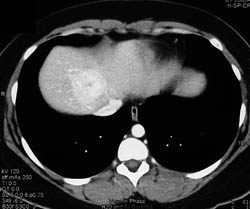

Tumor in Common Bile Duct